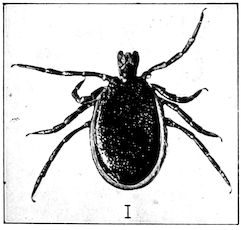

| Louping-ill | 429 | |||

| Suggested measures for prevention | 435 | |||